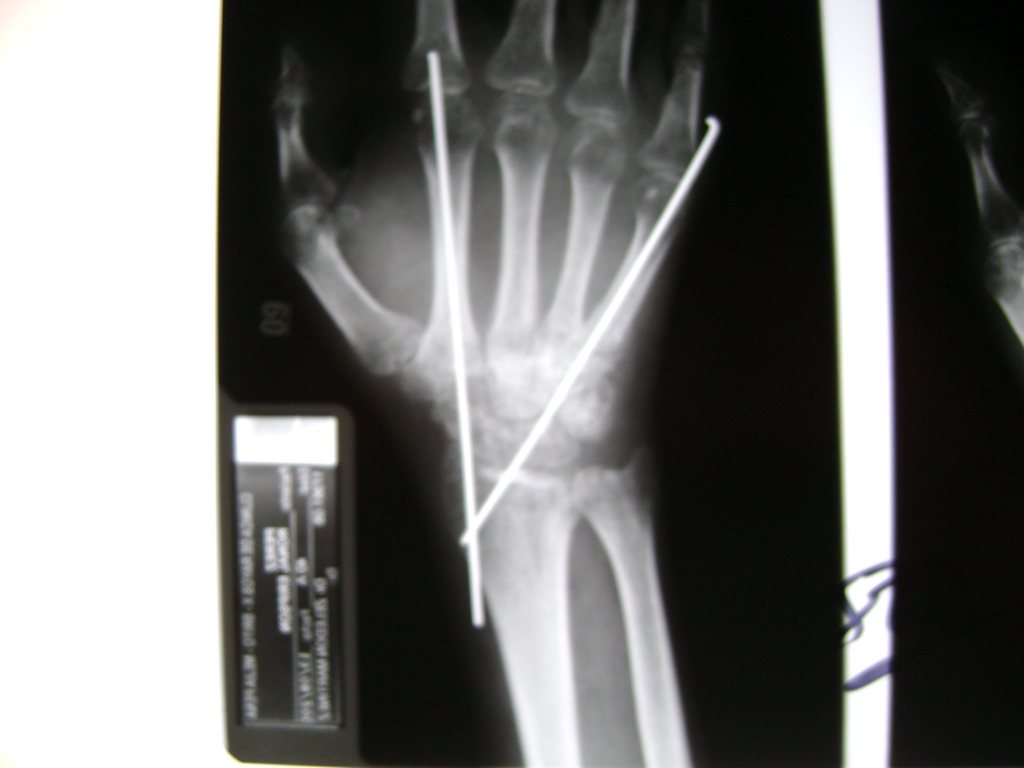

Calcaneo - Cirugías de Muñecas y Manos

Los procedimientos más comunes en cirugía de la mano son aquellos destinados a reparar traumatismos, incluyendo lesiones de tendones, nervios, vasos sanguíneos, y articulaciones; huesos fracturados; y quemaduras, cortes, y otros daños de la piel.